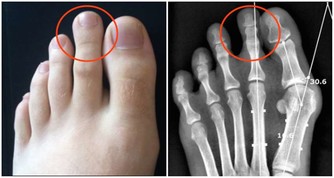

5少女頭髮黃

少女頭髮黃則可能由於缺鈣。青春期缺鈣主要表現為夜間盜汗,也就是睡覺時出汗;頭髮少,無光澤,呈焦黃狀;晚上睡覺時小腿肚子(腓腸肌)抽筋。